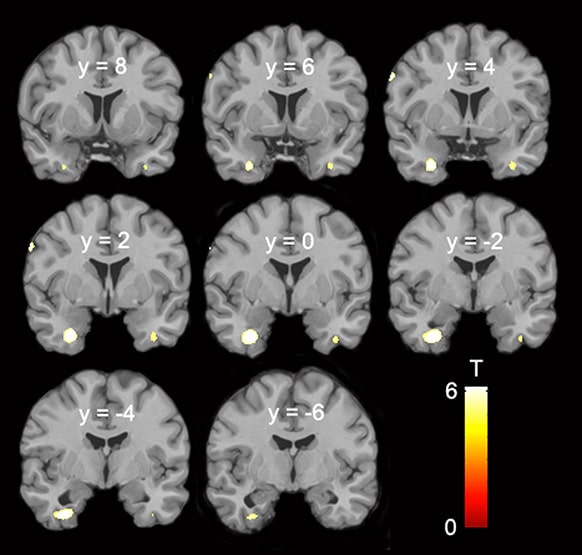

SLITRK Gen Ailesi, nöronal gelişimde önemli rol oynayan bir gen grubudur. Daha önce yapılan araştırmalarla bu gen ailesinin ‘Nöropsikiyatrik’ davranışlarda da önemli rol oynadığı da biliniyordu. SLITRK geninin Nöropsikiyatrik davranışlarda rol almasından yola çıkan araştırmacılar bu genin cinsel yönelimde de etkili olabileceği düşünerek SLITRK genini mercek altına aldılar ve genin özellikle hipotalamus ve talamus arasında yer alan Diensefalon’da(ara beyinde) aktif olarak çalıştığını buldular. Daha sonra yapılan beyin taramasında beynin bu bölgesindeki hücre yoğunluklarının homoseksüel ve heteroseksüel erkeklerde farklı olduğu tespit ettiler.

Homosexual Women Have Less Grey Matter in Perirhinal Cortex than Heterosexual Women